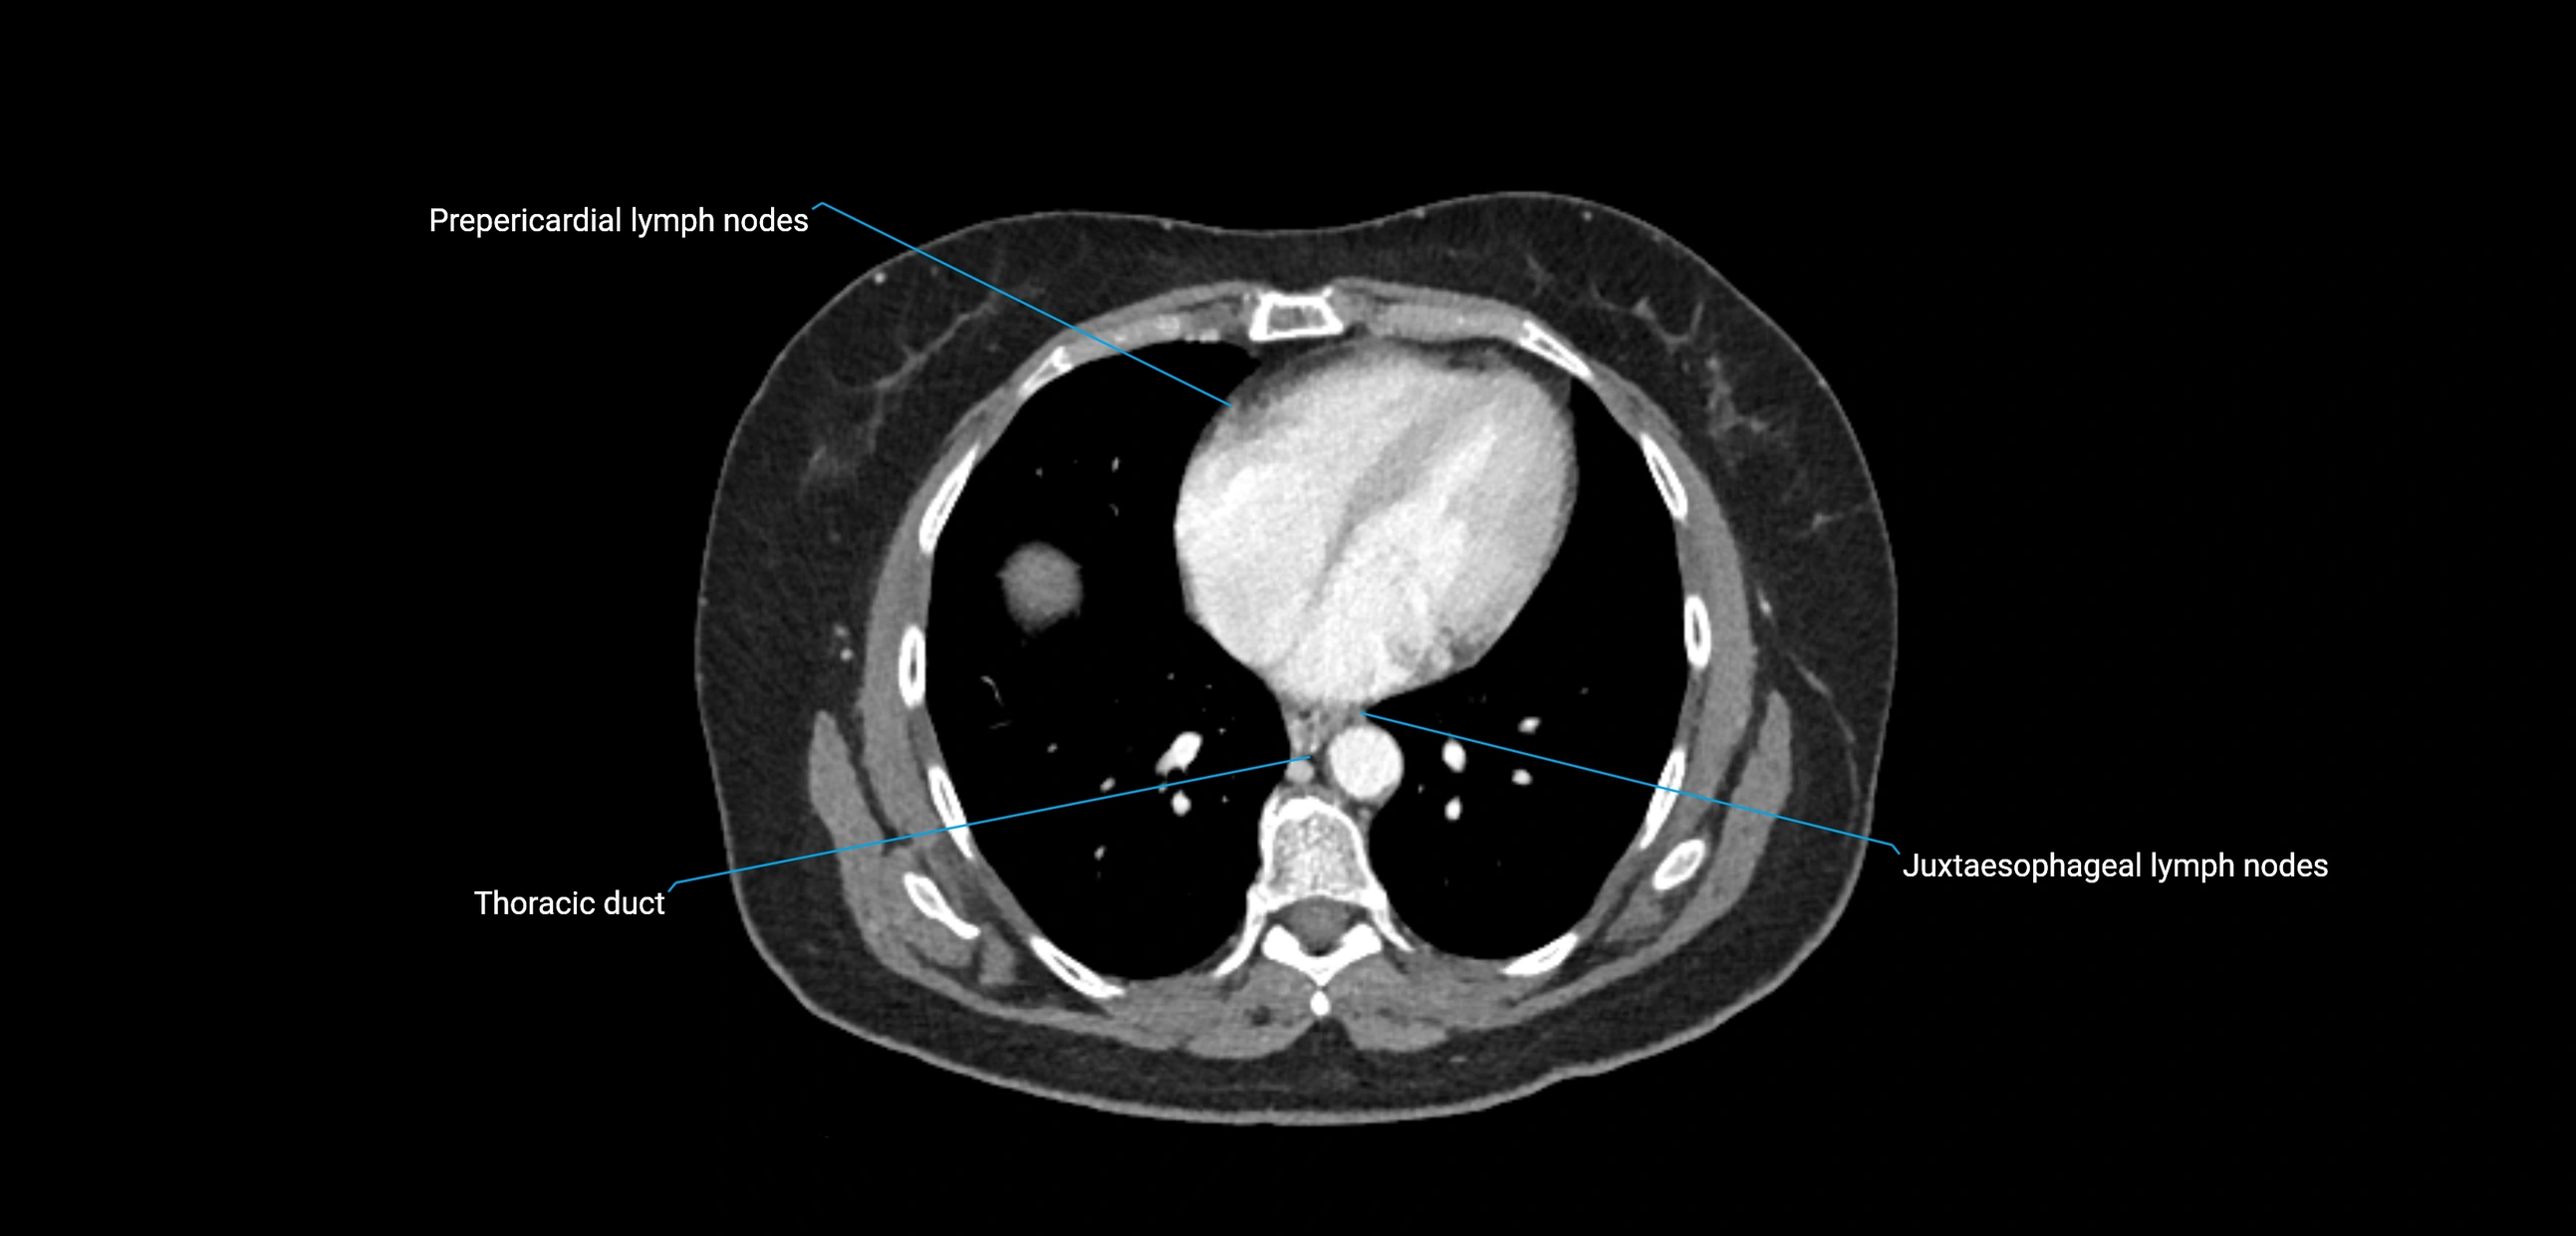

CT Appearance

CT Pre-Contrast:

• Nodes appear as soft-tissue density nodules adjacent to the aorta and IVC

• Calcification may be seen in chronic infections (e.g., tuberculosis)

CT Post-Contrast:

• Normal nodes enhance homogeneously

• Malignant nodes may show heterogeneous enhancement, central necrosis, or conglomerate formation

• Size >1 cm short axis is suspicious, though morphology and distribution are equally important

CT image

image